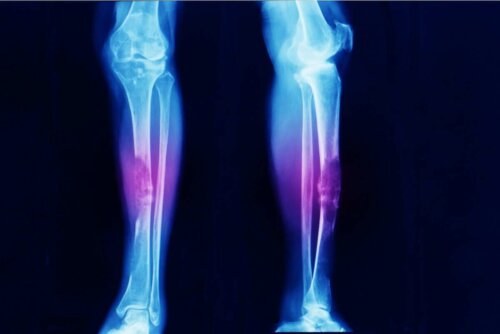

- Osteosarkom, adından da anlaşılacağı gibi kemik kanseridir.